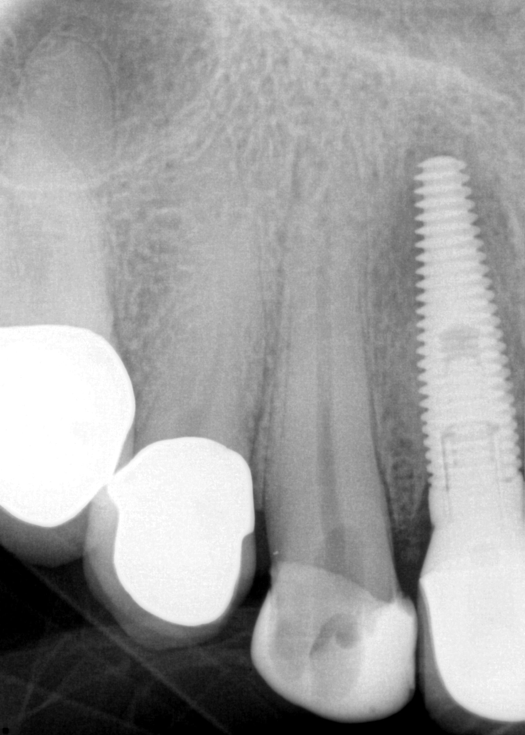

Fig 9. 33 days postoperative fiber-post placement and CAD crown.

Figure 9

The patient returned for final evaluation of the provisional calcium-hydroxide endodontic therapy and resolution of the infection (33 days postoperatively). Fistula was not present; the tooth was not sensitive to percussion or mastication. The gold crown was removed using a high-speed metal cutting bur, the remaining caries were excavated conservatively, and the endodontic therapy was completed. Placement of glass-fiber reinforced composite and composite core buildup took place. The natural tooth structure to receive the glass-fiber post and a long-term restoration was available (Figure 8). Within one appointment, the tooth was restored (Figure 9). The patient was instructed to return for clinical and radiographic evaluation after 6 to 12 months to determine progression of periodontal healing. At that time, if the healing were adequate and the tooth were stable, evaluation of the tooth would be considered every 3 to 4 years.7